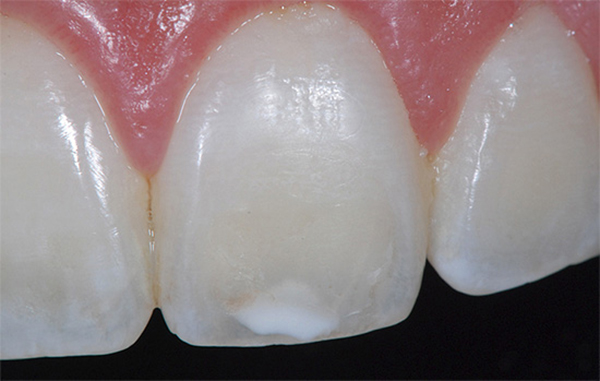

Фото 2. Знімок передніх зубів дорослої людини з почався на них карієсом у вигляді білої плями.

- Поява більш світлих ділянок на зубній емалі — ознаки першої стадії початкового карієсу.

Патологія має тенденцію до швидкого розвитку, і якщо спочатку вона практично ніяк не проявляється, за винятком зміни кольору зубної емалі (на ній з’являються більш світлі ділянки, які з часом темніють), то при відсутності терапії емаль продовжує руйнуватися, на ній з’являються вже добре помітні пошкодження.